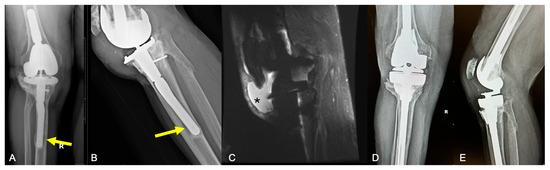

2.2.1. Endoprosthetic Aseptic Loosening

- Possibly loose involves radiolucent zones at greater than 50% but less than 100% of the cement–bone interface;

- Probably loose involves a continuous lucent line around 100% of the cement mantle without evidence of migration;

- Definitely loose involves migration of the cement or the implant.